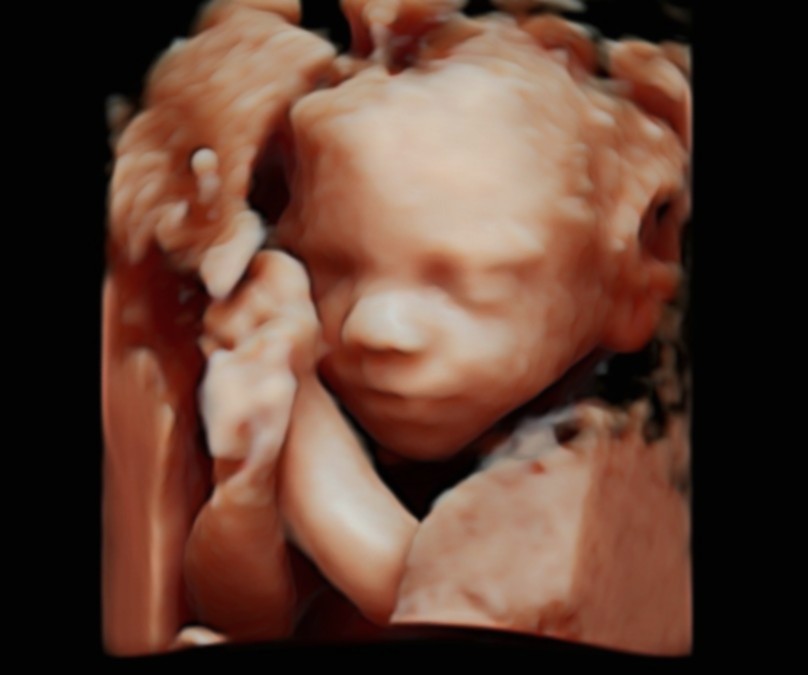

Anomaly Scan

Detailed fetal anatomy, placental assessment and Doppler screening—delivered within a consultant-led care pathway

The 20-week anomaly scan is a key milestone in pregnancy and the next major assessment after the nuchal scan. At this stage, your baby’s organs and structures are sufficiently developed to allow a detailed evaluation of growth and anatomy, helping to identify or rule out major structural conditions.